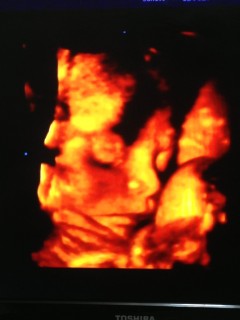

なかなか見れない週数に入りお顔を久々に見せてくれました!! 大きさは1860g程度、平均の大きさの女の子です。前回よりもお肉がついて赤ちゃんらしくなってきました。厚ぼったい唇は私に似ています。 目鼻立ちもしっかりしていると言われました!早く会いたくて仕方ないです。